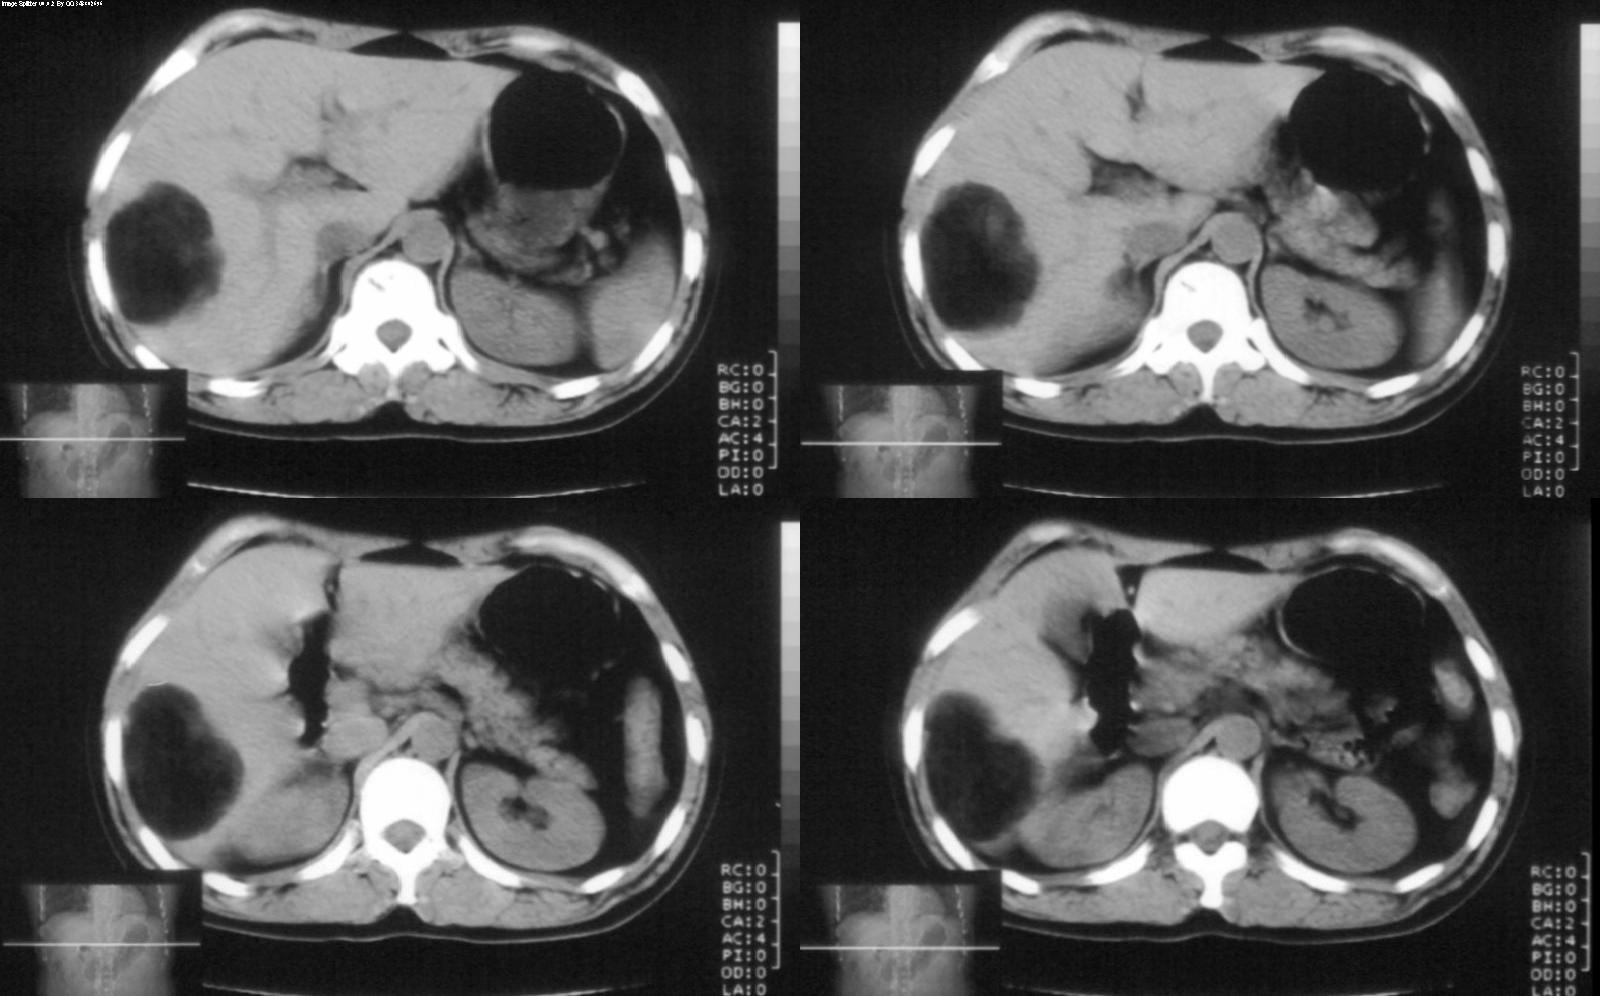

标题: CT28180:女性,42岁。体检时发占位。 [打印本页]

标题: CT28180:女性,42岁。体检时发占位。

ct值?肝脏血管平滑肌脂肪瘤

血管平滑肌脂肪瘤可能性大

考虑hcc>肝脏血管平滑肌脂肪瘤>肝脏髓脂瘤等,期待结果。

肝脏血管平滑肌脂肪瘤,边界结节样血管影持续性强化。

病灶多种成分,以脂肪为主,可见强化的血管肌肉成分,边界较清晰,综合考虑血管平滑肌脂肪瘤可能性大